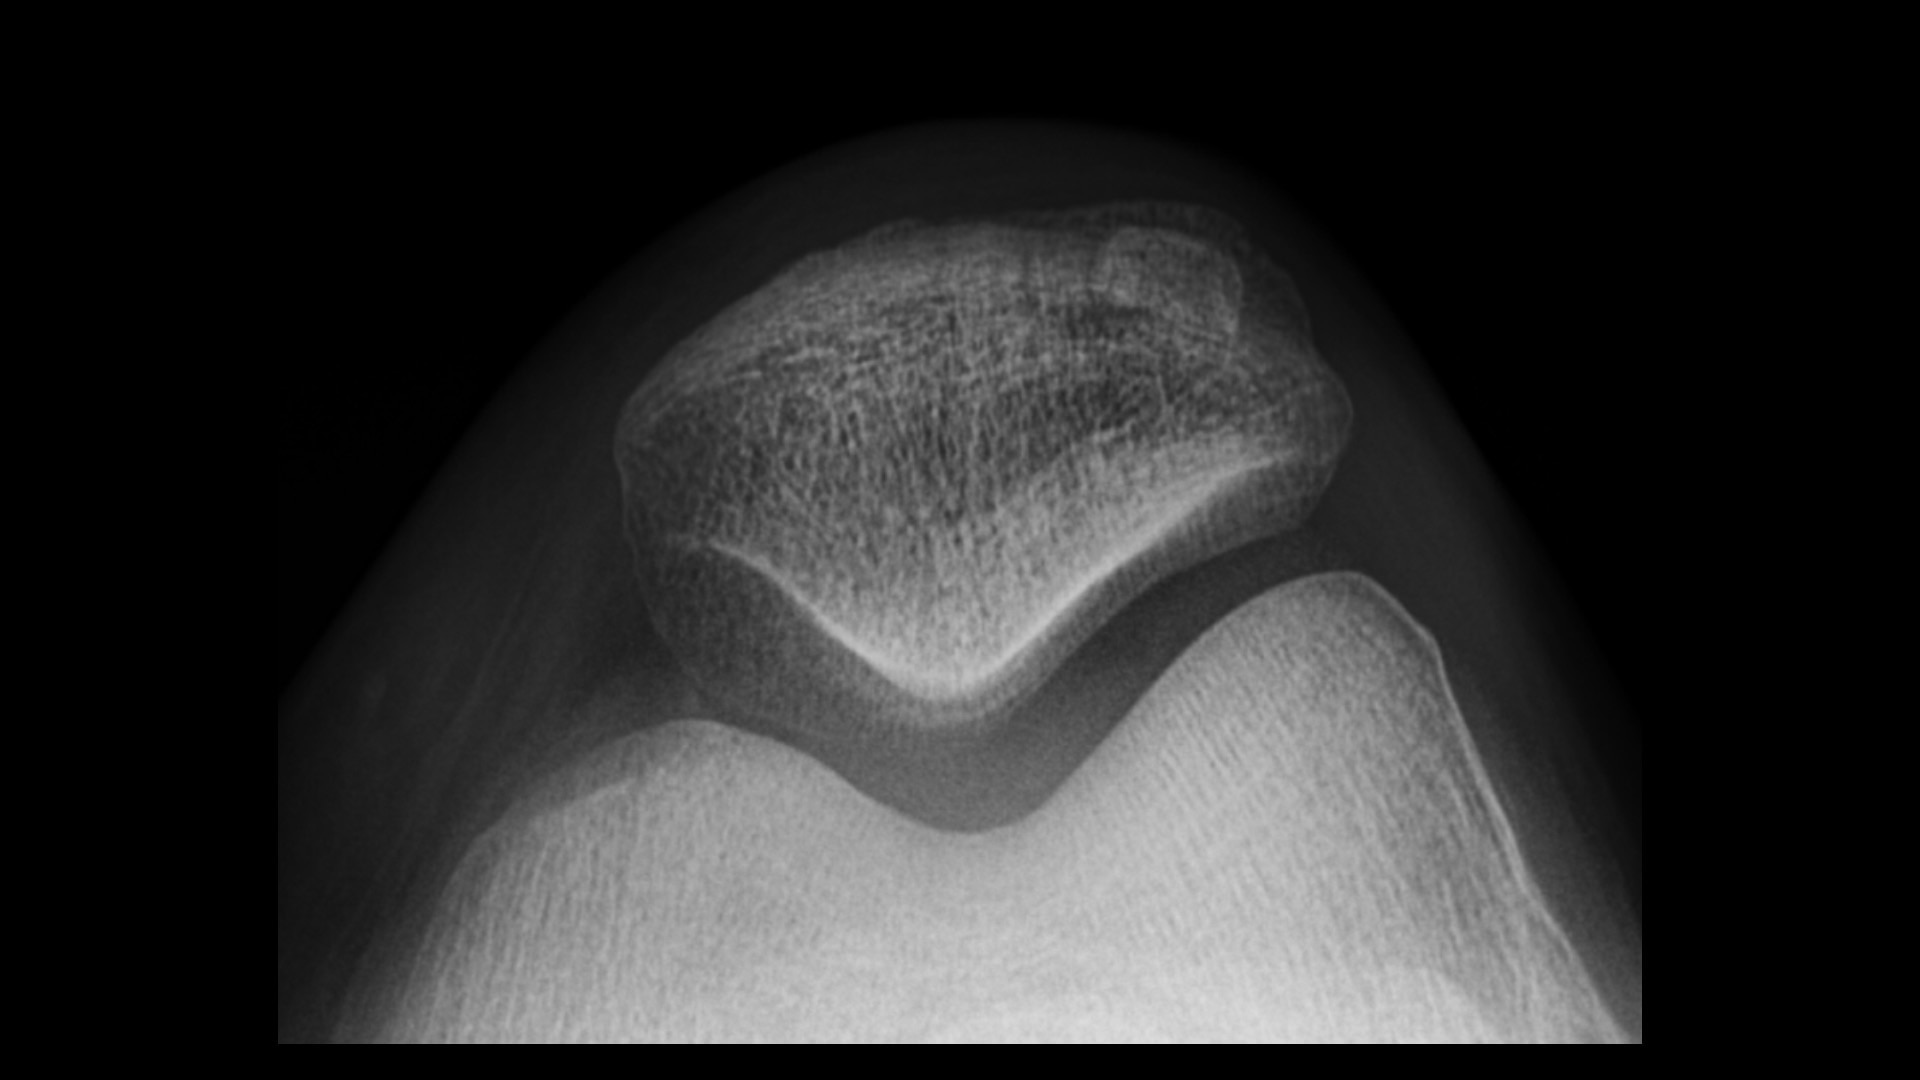

Advanced applications and IQ

Enable radiologists to consistently see more details and provide quality diagnosis